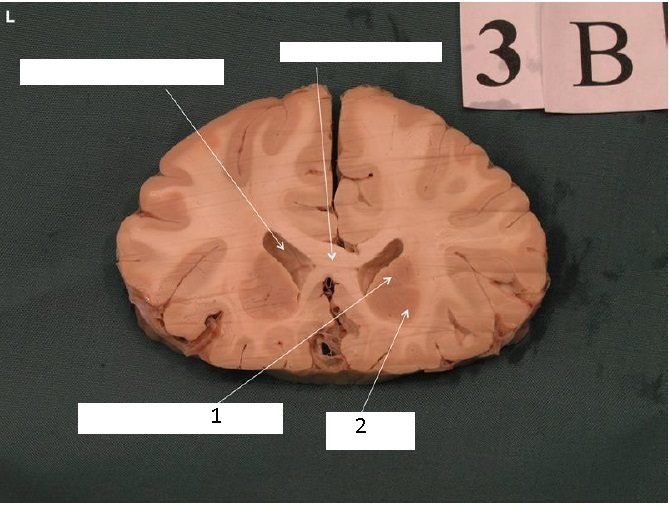

Identify 1

Body of Corpus Callosum

Identify 2

Cingulate Gyrus

Note: Cingulate gyrus + parahippocampal gyri = limbic system